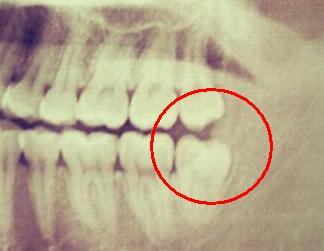

医生先让拍牙片,看看你的牙长成啥样,好决定怎么动手除掉它哈哈

只有这种正八经的懂事的牙才能免逃一劫!

而我也很“幸运”,是这种,水平阻生,必须经此一役战胜它。也是这一次,让我知道了我有多富,4颗智齿。然后开单去拿麻药,大战一触即发!